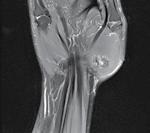

Reducerea artroscopică și fixarea internă a unei fracturi articulare cominutive de epifiză distală de radius cu fragment „die-punch”- prezentare de caz Dr. Daniel Vîlcioiu, Claudiu Jaba